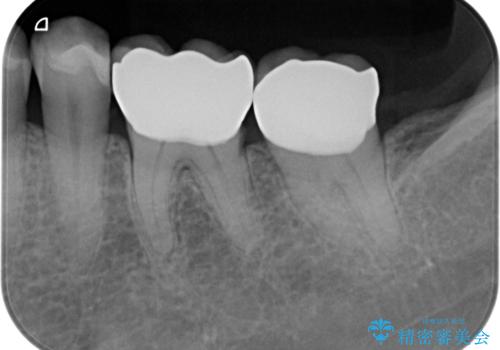

- 「長年使っている奥歯の目立つ銀歯を白くしたい。」、と希望され来院されました。

銀歯を丁寧に除去し、このように銀の覆っている面積が多い場合は、インレータイプではなくより強度に優れ歯もセラミックも長持ちするジルコニアクラウンでの治療を計画します。

- 26.4万円(ジルコニアクラウン×2・仮歯×2)費用は治療当時の料金となります

天然歯のような白さのセラミッククラウンで、歯本来の審美性を回復することができました。